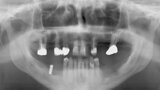

Fig. 1: Initial situation: severe bone defects and implant in situ.